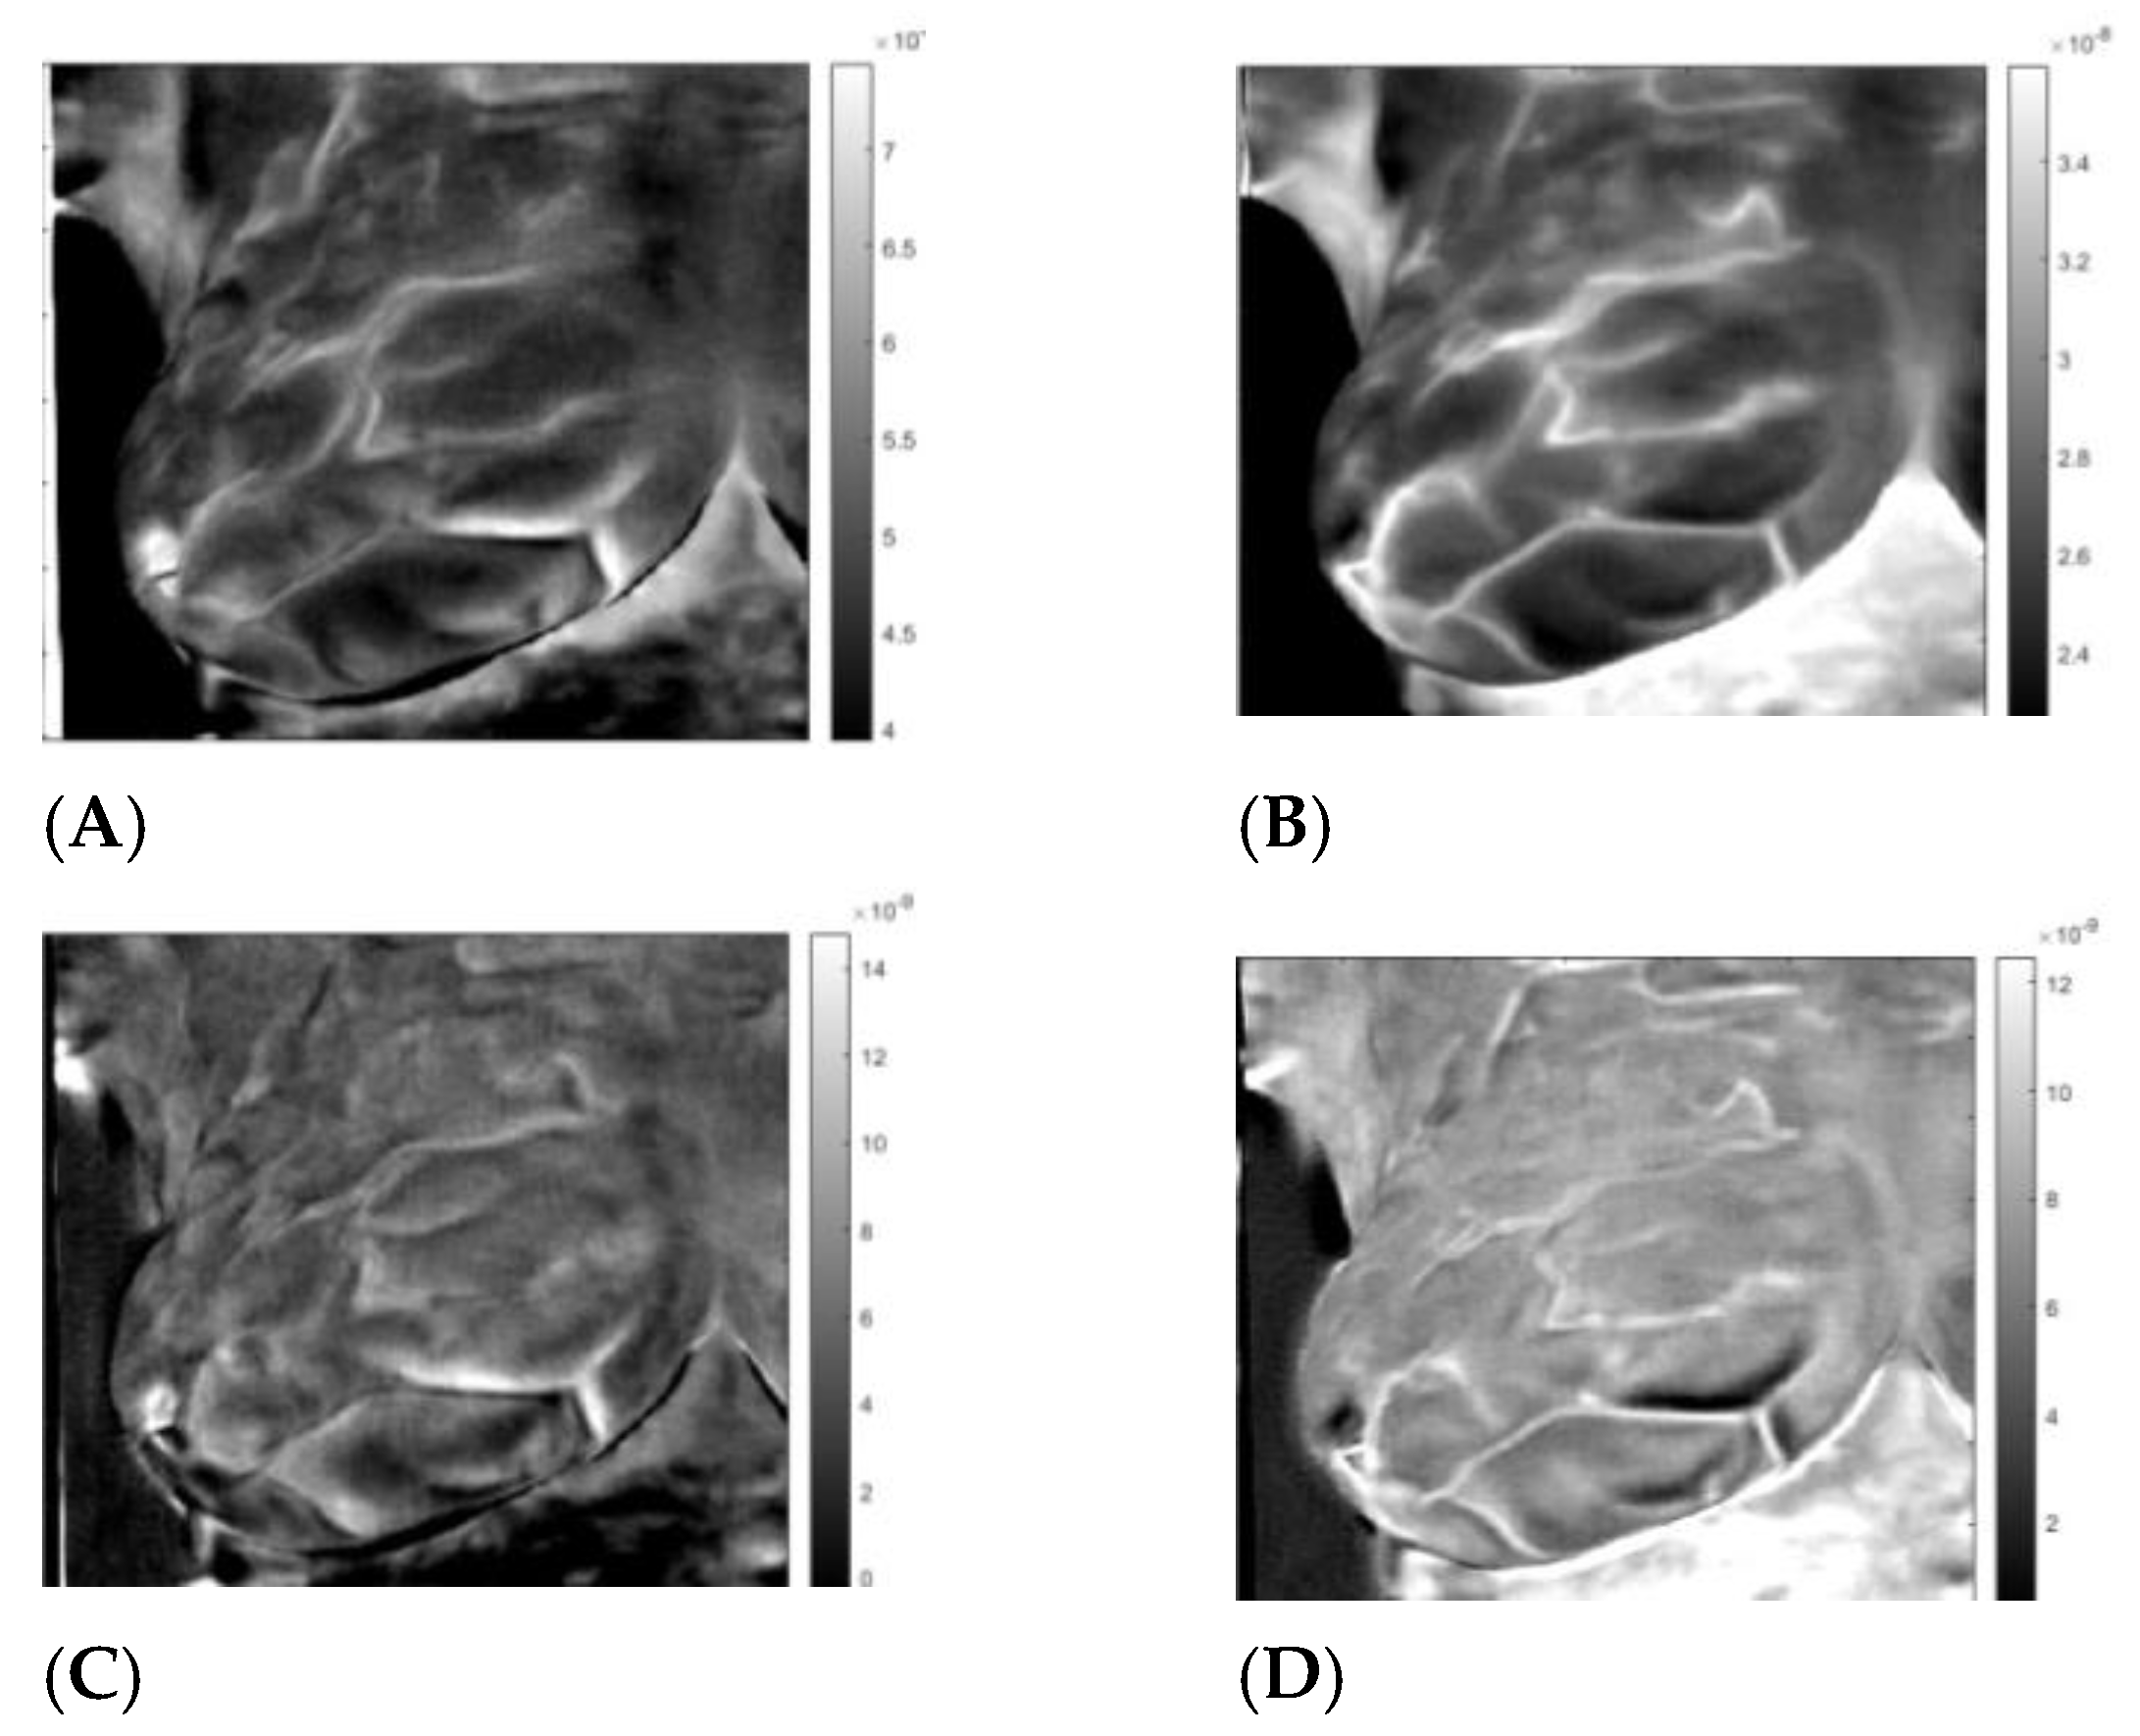

3.3. Analysis

Appendix B. Matrix Factorization